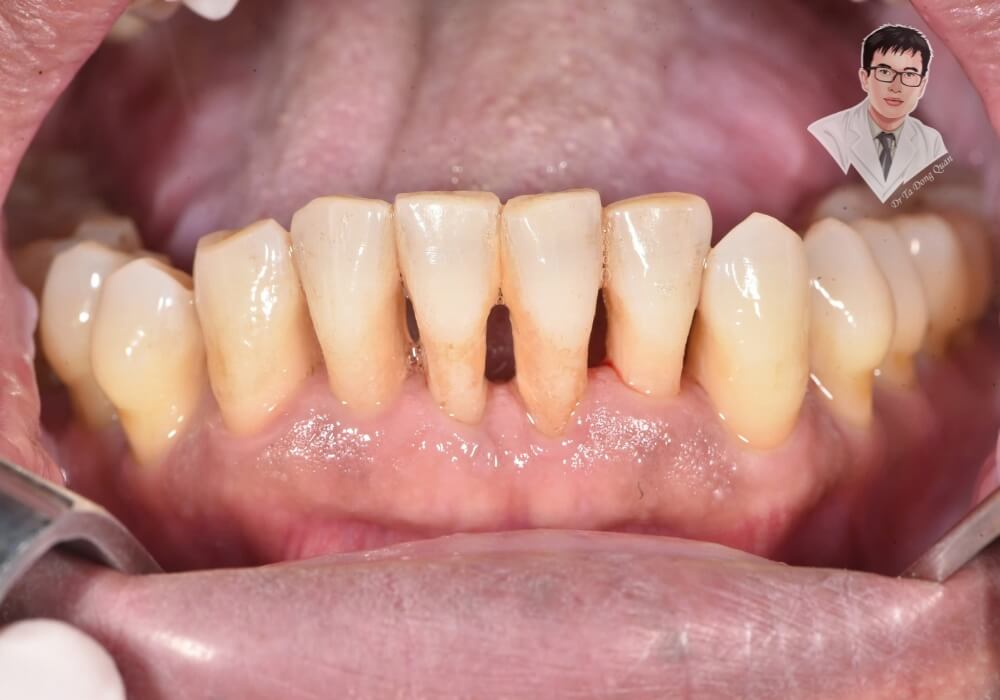

Tụt nướu răng là tình trạng mô nướu bị co rút, làm lộ chân răng và tạo khoảng trống giữa răng và nướu. Điều này khiến vi khuẩn dễ xâm nhập, làm tăng nguy cơ sâu răng, viêm nha chu và có thể dẫn đến mất răng nếu không được điều trị kịp thời. Không chỉ ảnh hưởng đến sức khỏe răng miệng, tụt nướu còn làm giảm thẩm mỹ, khiến răng trông dài hơn và dễ bị ê buốt khi tiếp xúc với thực phẩm nóng, lạnh.

Tụt nướu làm lộ chân răng, khiến răng trông dài hơn bình thường. Điều này không chỉ ảnh hưởng đến sự cân đối của hàm răng mà còn khiến nụ cười kém tự nhiên. Với những người có nướu răng mỏng, tình trạng này càng dễ nhận thấy, làm giảm sự tự tin trong giao tiếp.

2. Gây ê buốt và nhạy cảm với thức ăn

1. Tụt nướu nghiêm trọng, lộ chân răng nhiều

Nếu bạn nhận thấy nướu bị co rút đáng kể, làm lộ chân răng nhiều hơn bình thường, đây có thể là dấu hiệu cảnh báo tụt nướu ở mức độ nghiêm trọng. Khi chân răng tiếp xúc với môi trường bên ngoài, răng trở nên nhạy cảm hơn và dễ bị tổn thương. Trong trường hợp này, cần đến gặp nha sĩ để đánh giá mức độ tụt nướu và đưa ra phương án điều trị phù hợp.